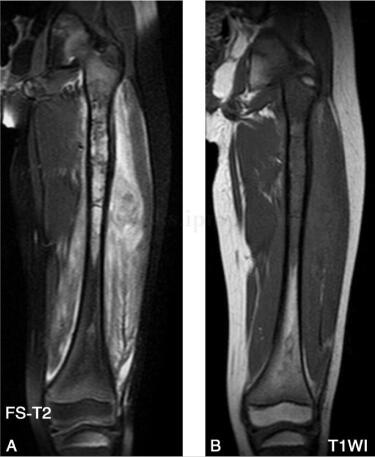

女,5岁,左下肢疼痛月余,近日加重,左下肢活动受限。病来无发热盗汗,无结核接触史。查体:左大腿肿胀,皮温略高,有压痛(图1、图2)。

图2 MR:左股骨中上段髓腔内见长T1、长T2信号改变,局部肿胀增粗,左股骨局部外侧缘见层状骨膜反应,周围肌肉组织呈长T1、长T2信号改变